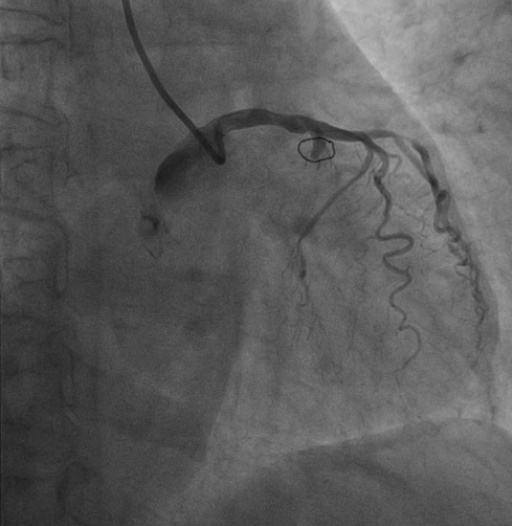

急性心肌梗死发病急、病情凶险、死亡率高,是导致中老年人猝死的主要原因之一,当高龄老人遭遇急性心梗时,凶险更是不言而喻。近日,我院心血管内科成功救治一名90岁高龄的心肌梗死患者,术后患者康复出院并送来锦旗。这是我院心肌梗死患者中年龄最大、成功完成急诊PCI手术的女性患者。

80岁以上的患者,因身体的各种功能明显衰退,行心脏支架植入术风险很大,几乎是手术的雷区。但如果不进行介入精准治疗,延误了最佳的治疗时机,心肌坏死情况可能会加重,随时有生命危险。心肌梗死猝死率较高,越早治疗,效果越好。